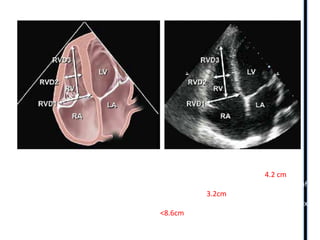

The basal diameter is the maximal short-axis dimension in the basal

one third of the RV . The upper reference limit for the RV basal dimension is 4.2 cm

The midcavity diameter is measured in the middle third of the right ventricle at the level of

the RV papillary muscles. Normal <3.2cm

The longitudinal dimension is drawn from the plane of the tricuspid annulus to the RV apex

Normal<8.6cm